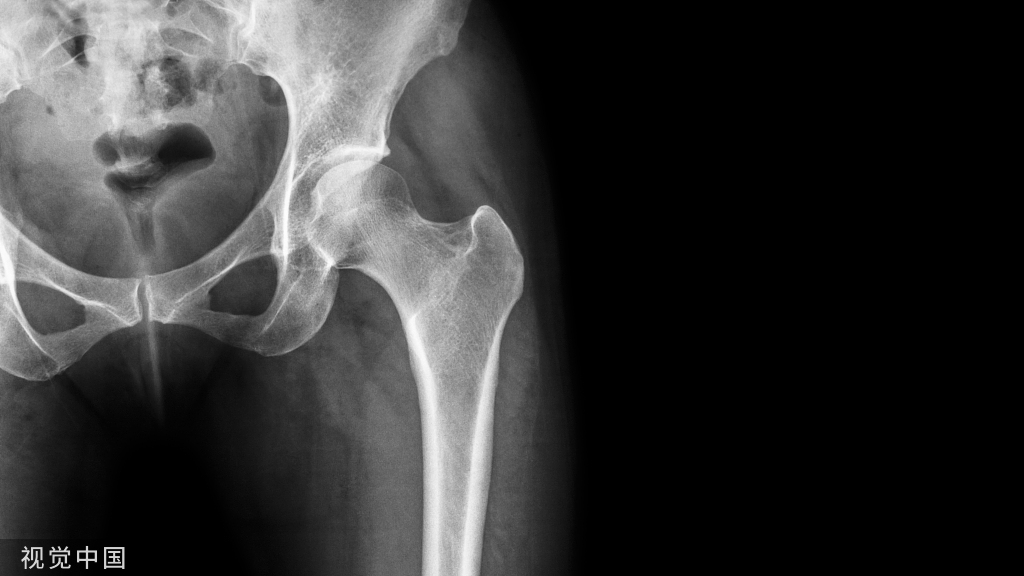

二、膝关节软骨损伤的定义、症状及体征

本指南所指的膝关节软骨损伤是由创伤引起的急慢性关节软骨损伤[2,3]。若损伤仅累及软骨层,称为软骨损伤,若损伤同时累及软骨及软骨下骨层,则称为骨软骨损伤。膝关节软骨损伤症状主要表现为关节疼痛、肿胀、交锁、弹响、打软腿,在体征方面主要表现为关节压痛、活动受限、捻发音等[2,4]。本指南涉及的软骨损伤的急性期定义为受伤后一个月内。

临床问题1:膝关节软骨损伤的影像学诊断标准是什么?

推荐意见:膝关节软骨损伤的影像学检查常规建议磁共振成像(MRI)平扫作为首选,其次为磁共振关节腔造影(MRA)检查。若存在金属植入物等无法完成MRI检查时推荐计算机断层扫描(CT)关节腔造影检查为首选检查。分级系统采用国际软骨修复协会(ICRS)改良磁共振成像分级系统。(A级,强推荐)(表1)。